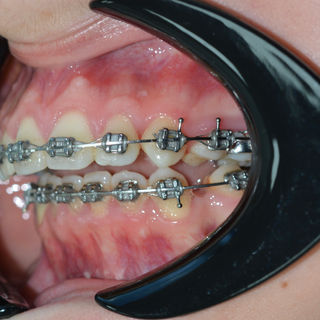

Paciente Clase II al cual se le realizó una cirugía sagital bilateral de rama y mentoplastía, para lograr una correcta proyección sagital facial y un centrado mandibular, mejorando la estética, función y componente psicológico.